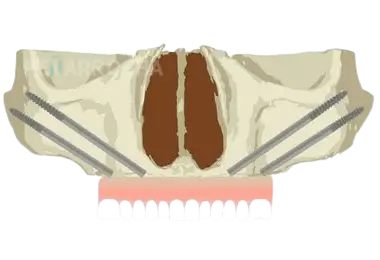

Técnica híbrida (convencional + cigomáticos)

Se colocan dos implantes cigomáticos en la parte posterior y dos o cuatro implantes convencionales en la parte anterior del maxilar.

Se recomienda en los casos donde existe una extrema atrofia en zona posterior y una atrofia ósea moderada en la zona anterior, donde aún es posible colocar al menos dos implantes en las zonas caninas.

Técnica cigomática total (quad zygoma)

Se colocan cuatro implantes cigomáticos, dos en cada lado, sin necesidad de implantes convencionales.

Se emplea en pacientes con atrofia extrema donde no hay hueso maxilar suficiente para implantes convencionales.